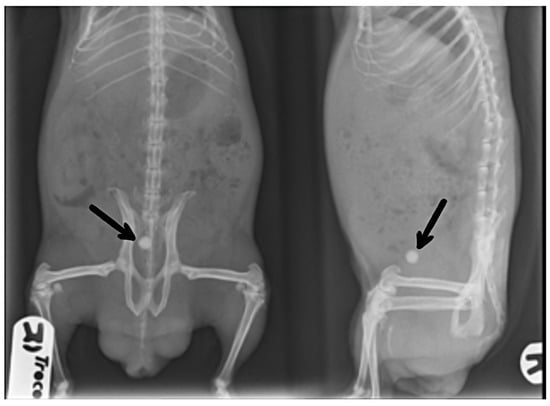

The radiographic study permitted the observation of uroliths in the guinea pig population studied: in 28 cases, the urolith was located in the bladder (Figure 1), with 14 cases of it in the urethra and 7 cases of it in the ureter. In addition, three animals had more than one urolith (one in the urethra and another one in the ureter). In male guinea pigs, most uroliths were located in the bladder (n = 23), while in females, most were associated with the urethra (n = 13), revealing a significant association between sex and anatomical location (p = 0.001; data not presented).

Figure 1. Radiographs of a sedated male guinea pig with an urolith in the bladder (marked with arrows) in ventrodorsal and right latero-lateral projections.